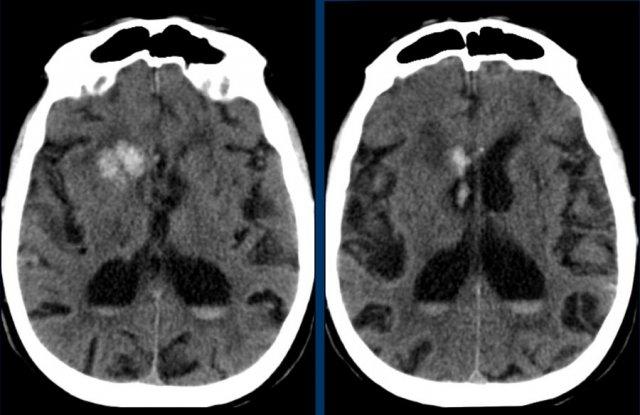

Nhân đuôi

Các hình ảnh cho thấy xuất huyết tại hạch nền ở bệnh nhân tăng huyết áp lâu năm.

Tổn thương nằm tại đầu nhân đuôi.

Đầu nhân đuôi nhận máu từ động mạch Heubner và các động mạch thấu kính-vân.

Vỡ các động mạch này gây xuất huyết nhu mô não.

Sự hiện diện của tụ máu trong não thất được coi là yếu tố tiên lượng xấu do tắc nghẽn lưu thông dịch não tủy gây não úng thủy và tăng áp lực nội sọ.